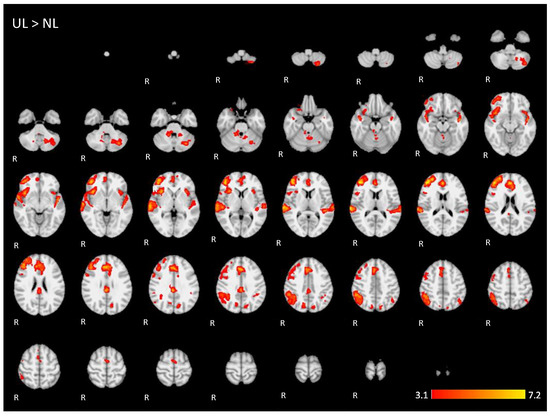

Appendix A. The 2D fMRI Maps of All Brain Slices for Both Active Conditions (NL, UL) and for Both Contrasts (NL > UL and UL > NL)

| UL > NL | 6.1 | 44 | 44 | 14 | Right middle frontal gyrus |

| 5.57 | 2 | 42 | 20 | Right Paracingulate Gyrus | |

| 4.94 | 50 | −42 | 44 | Right supramarginal gyrus, posterior division | |

| 5.01 | −48 | −12 | −6 | Left superior temporal gyrus | |

| 5.08 | −32 | −68 | −34 | Posterior lobe of left cerebellum | |

| 5.18 | 4 | −32 | 30 | Right cingulate gyrus, posterior division | |

| 4.32 | 16 | −46 | −32 | Anterior lobe of right cerebellum | |

| 4.3 | −12 | −74 | 28 | Left cuneus/precuneus cortex | |

| 3.7 | −8 | −54 | −26 | Anterior lobe of left cerebellum | |

| 4.62 | −28 | −70 | −60 | Left cerebellum | |

| 4.11 | −46 | −60 | 48 | Left angular gyrus/inferior parietal lobule | |

| 4.43 | 12 | −68 | 40 | Right precuneus cortex | |